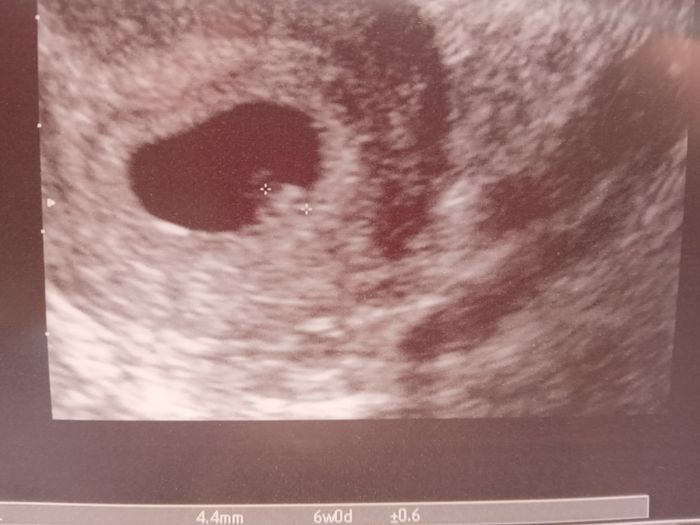

Il lunedì 5/6 poi mi sono decisa a chiamare la ginecologa che mi ha dato appuntamento per il sabato appena trascorso,ed ecco a voi che vi presento appunto il mio secondo miracolo!❤

Specifico,per chi non lo sapesse,che mi era stato diagnosticato utero didelfo,in sede di cesareo mi dissero che non era così ma che avevo un setto completo e che mi era stato rimosso,con questa eco la ginecologa ha visto che invece c'è ancora una netta differenza tra destra e sinistra e si vedono nitidi i due uteri,quindi l'unica sua soluzione è che mi sia stato rimosso un setto dentro la cavità uterina dove c'era la gravidanza e vuole approfondire la situazione con chi mi ha operato ecc ecc...rimane sempre tutto un grande mistero😅ma l'importante è che vada tutto bene come con il mio primo grande amore❤🙏🍀